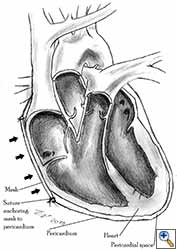

Video 1 depicts a pericardial reconstruction with Marlex after a right completion pneumonectomy with pericardiectomy for lung adenocarcinoma (see also Figure 1). The technique of pericardial reconstruction after the resection of invasive mediastinal tumours is illustrated in Figures 8a-c). Video 2 depicts a pericardial reconstruction with Mersilene mesh after the resection of a malignant thymoma invading the anterior pericardium (see also Figure 4b). The technique of right pericardial reconstruction after extrapleural pneumonectomy is illustrated in Figures 9a and 9b). Video 3 depicts a pericardial reconstruction using Gore-Tex Dual Mesh after a left extrapleural pneumonectomy (see also Figure 3). Care must be taken to prevent constriction (Figure 10).

| Figure 10a: Concept of geometric pericardial reconstruction. | Figure 10b: Non-geometric pericardial reconstruction can lead to cardiac tamponade. |

- The pericardium must be reconstructed in a geometric, tridimensional fashion to avoid constriction (Figures 10a, 10b).

Tamponade physiology results after a tight pericardioplasty that restricts ventricular filling. It has been reported after pericardial reconstructions following extrapleural pneumonectomy for diffuse malignant mesothelioma [4]. The treatment is surgical reintervention and geometrical reconstruction. Postoperative cardiac tamponade can also develop after not fenestrating impermeable prosthetic material [4]. The treatment is emergency decompressive pericardial drainage.